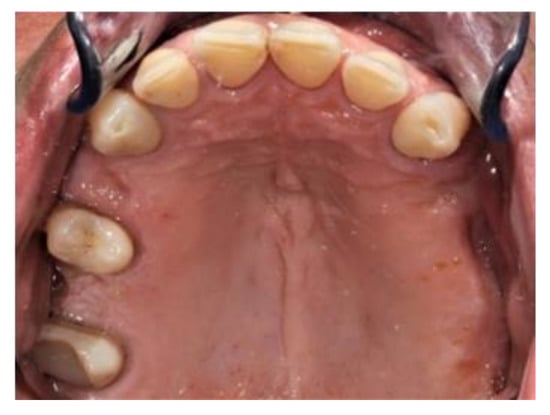

2. Case Report

The subject involved in this clinical study was a healthy woman, 54 years old. The request of this patient was to improve her mouth both functionally and aesthetically, which was altered because of the partial edentulism (Kennedy Class II). She asked to avoid any invasive surgery. During the anamnesis, she declared not to be affected by any systemic pathology (e.g., diabetes, hypercholesterolemia or hypertension). She also declared not to be affected by an allergy to any medication or similar drugs; she declared not to be subjected to any pharmacologic treatment except some analgesic therapy to treat sporadic headaches. The patient claimed to smoke 20 cigarettes a day for more than 20 years. The next step was to perform an objective examination, associated with a series of intraoral pictures (Figure 1, Figure 2, Figure 3, Figure 4 and Figure 5) and to the analysis of a radiographic exam (orthopantomography, Figure 6) that was acquired 10 months earlier when the same subject underwent the therapy and the teeth extraction 4.7–4.8. The objective examination showed poor oral hygiene, with plaque accumulation as well as the presence of many pigmentations due to excessive smoking. The radiography showed bilateral bone atrophy together with periodontal damage for most of the residual dental elements. These conditions represented a limitation to the insertion of implants for a fixed prosthesis.

Figure 4. Upper view.

Prosthesis 03 00038 g004